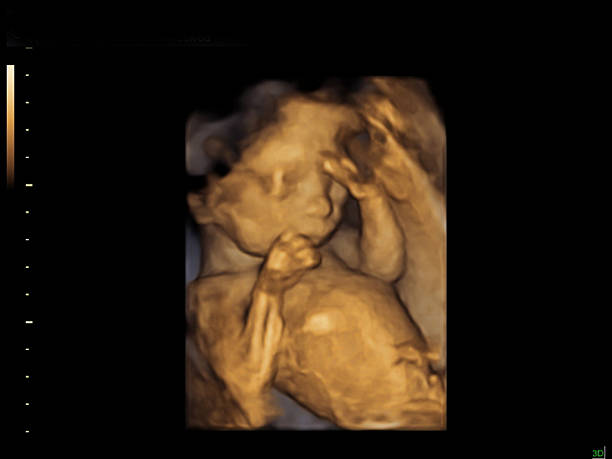

女方客户档案(J女士),患者年龄:38岁,卵巢功能减退,激素值异常,既往顺产一胎,产后多年未避孕但始终未孕,本次为明确计划二胎而就诊,进周当月检查卵巢储备情况,AMH:0.457 ng/mL(极低值),FSH:22.60 mIU/mL(远超正常范围),高度卵巢反应低下(Poor Ovarian Response, POR)典型表现